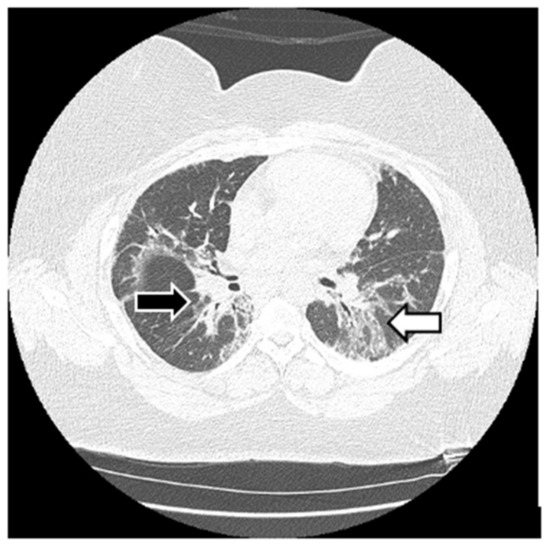

6.2. Histopathologic and Radiographic Findings in Myositis-Associated ILD